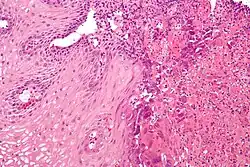

A esofagite consiste na inflamação da mucosa que recobre o interior do esôfago. Pode vir acompanhada de um estreitamento no interior do conduto (estenose esofágica).

É uma doença inflamatória com características alérgicas, causada por um denso infiltrado de eosinófilos no epitélio esofágico. O diagnóstico é feito por endoscopia digestiva alta, com identificação de lesões sugestivas e realização de biópsias. A análise destas amostras deve demonstrar a presença de pelo menos 15 eosinófilos por campo de grande aumento. O tratamento baseia-se em dietas específicas bem como medicamentos como corticóides.[1]